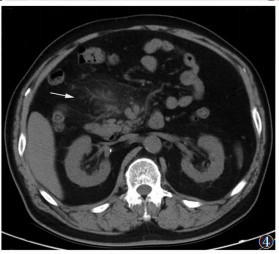

2.2 MSCT表现Ⅰ型病灶表现为肠系膜血管根部局限的呈靶环样或同心圆样分布的磨玻璃影,直径<0.5 cm,病灶围绕肠系膜血管向外放散,病灶间可见正常的肠系膜脂肪组织,平扫时CT值为-87~-75 HU,增强扫描病灶无明显强化(图 1,2),CT值较平扫增加7~15 HU。Ⅱ型病灶范围较Ⅰ型增大,多呈片状分布,病变内无正常脂肪组织,其内可见长索条,病变与远处正常脂肪组织间存在明显的分界线(图 3),病变的磨玻璃密度较Ⅰ型更高,病灶直径 > 1 cm,平扫时CT值-35~-27 HU,增强扫描病灶血管显示清晰,但无狭窄、无变形,病灶远端分界线呈索条样强化(图 4),病灶包含强化的血管,CT值增加17~34 HU。Ⅲ型病灶多呈包裹态,界限明显,外缘可见类似的假包膜,多为线样高密度索条,病灶内肠管及肠系膜血管包裹明显,扭曲变形(图 5,6),系膜组织回缩,严重者可见假包块形成,增强扫描包块呈不均匀性的轻度强化,强化幅度 > 30 HU,动脉期强化程度低于门脉期及延迟期。

| 图 3 男,27岁,肠系膜脂膜炎,左半区肠系膜可见呈片状分布的磨玻璃影(白箭),病变内无正常脂肪组织 |

3.2 MSCT表现肠系膜脂肪代谢异常时MSCT均可见腹腔内脂肪组织多于正常人群,且脂肪组织越多,其发病率越高。不同分型肠系膜脂肪代谢异常的MSCT表现:①肠系膜脂肪营养不良,由于肠系膜解剖分布呈扇形,其扇轴位置是腹主动脉及其分支,扇面远端附着于结肠及小肠系膜,病变分布区域分为扇轴及扇面2处,因此表现为肠系膜血管根部脂肪密度增高,呈靶环样或同心圆样分布的磨玻璃影,病灶围绕肠系膜血管向外放散,病灶间可见正常的肠系膜脂肪组织将其分隔,增强扫描病灶无明显强化,该阶段脂肪细胞坏死多于炎细胞浸润及纤维增生。②肠系膜脂膜炎,MSCT示病变范围较肠系膜脂肪营养不良增大,多呈片状分布,病变内无正常脂肪组织出现,脂肪密度被磨玻璃影取代,其内可见长索条,但与远处正常脂肪组织间存在明显分界线,病变磨玻璃密度较肠系膜脂肪营养不良更高,增强扫描病变区血管显示清晰,但无狭窄、无变形,病灶远端分界线呈细线样强化[6-8]。③回缩性脂膜炎,病变多呈包裹态,与邻近组织有明显的界限,外缘可见类似的假包膜,多为线样高密度索条,病变内可见淋巴结增大,肠管及肠系膜血管包裹明显,分布杂乱,扭曲变形,系膜组织回缩增厚,严重者可形成假包块,增强扫描包块呈不均匀轻度强化[9-12]。